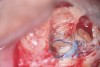

Fig 16. 3-mm root resection with methylene blue staining.

Figure 16

Fig 17. Retro-preparation with ultrasonic tip.

Figure 17

Fig 18. MTA placed as a retro-filling.

Figure 18

Clinical procedure: In the case of a root-end filling (Figure 15), once the apical 3 mm of the root has been resected (Figure 16) the canal system is then opened and cleaned with surgical ultrasonic tips to create the retro-preparation (Figure 17). After this is completed, the retro-preparation is dried and MTA is then placed and condensed in that space creating the retro-filling (Figure 18 through Figure 20).